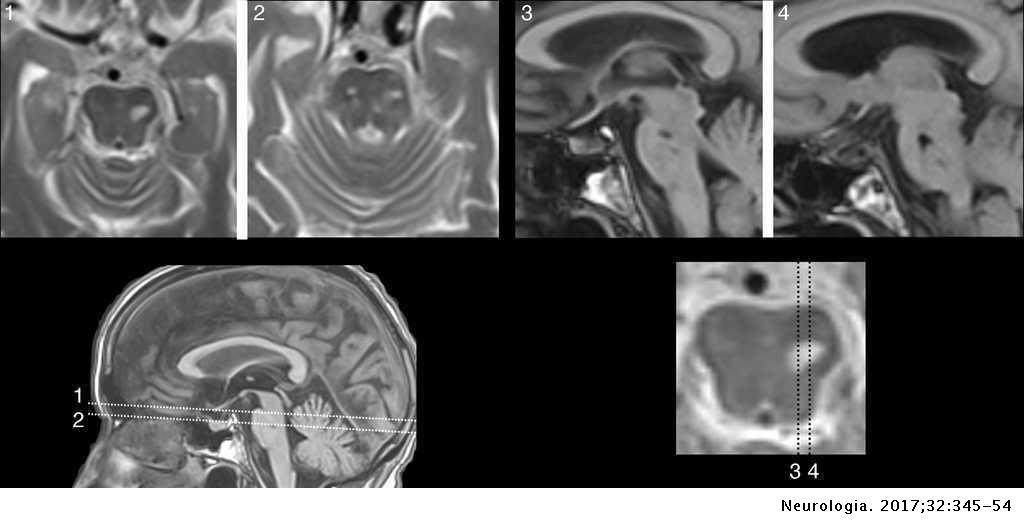

Auditory Hallucinations In Cognitive Neurology Neurologia